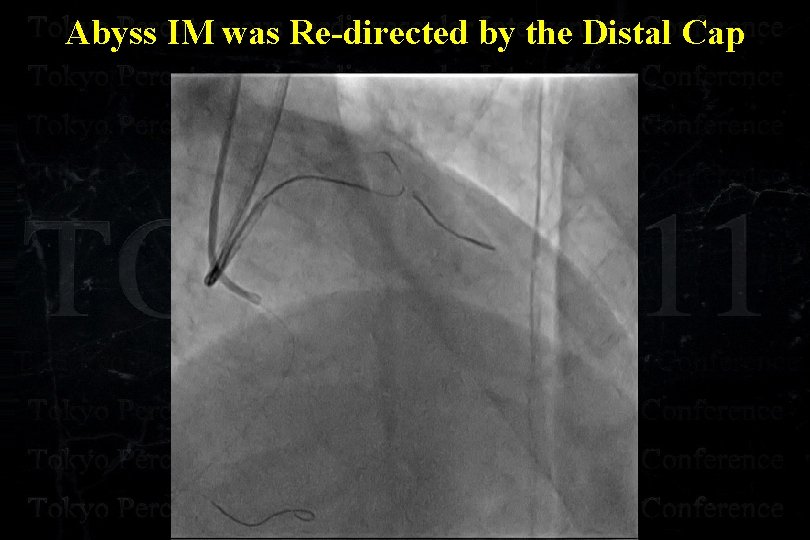

Abyss IM was Re-directed by the Distal Cap